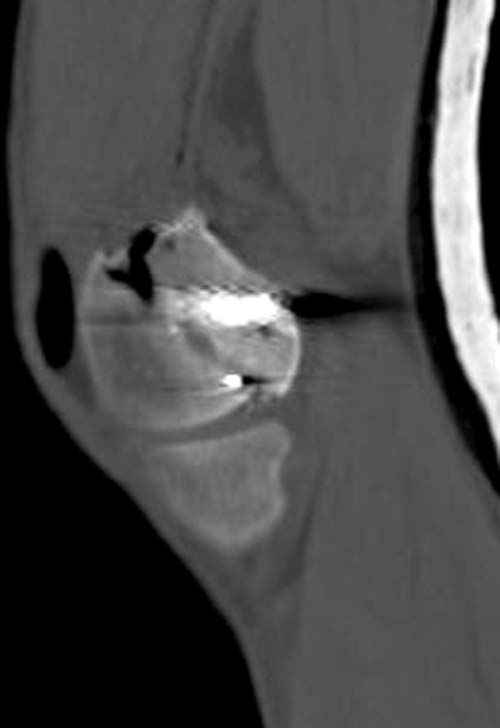

У молодого человека огнестрельное слепое ранение н/3 правого бедра. Поступил в клинику с внутрисуставным многооскольчатым Т-отразным переломом дистального отдела бедренной кости. Дополнительно на СТ-исследовании обнаружен перелом внутреннего мыщелка Hoffa со смещением.

Больной взят в операционную на второй день, где из небольшого медиального доступа выполнена артротомия коленного сустава. Произведена репозиция отломков, фиксация винтами. Попутно удалена пуля. Первым делом была достигнута репозиция медиального мыщелка (перелома Hoffa, где коронарная плоскость перелома трудно поддается закрытой репозиции и фиксации. ) Затем была достигнута идеальная репозиция суставной поверхности бедра и фиксация компрессирующими headless screws.

Дистальный отдел бедра был дополнительно фиксирован buttress пластиной с медиальной стороны из того же разреза. Для усиления фиксации латеральной колонны - с латеральной стороны закрытым способом из минидоступа установлена еще buttress plate. Пулевой канал дополнительно не подвергался хирургической обработке.